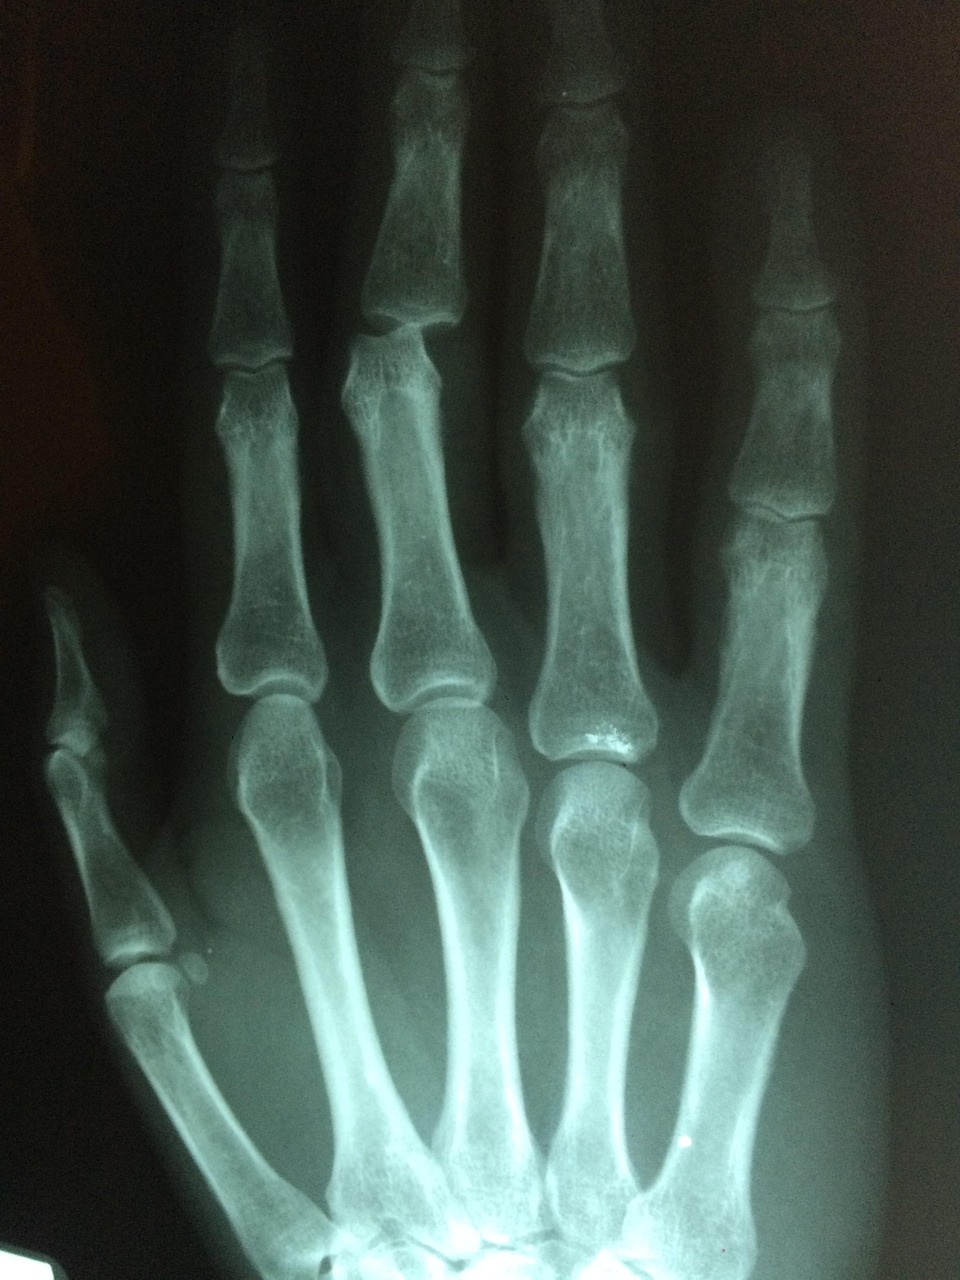

콜리스 골절의 진단

2. 방사선 검사

- X-Ray : 기본적인 골절 확인 방법

- CT촬영 : 복잡한 골절이나 관절 침범 여부 확인

- MRI촬영 : 연부조직 손상 확인(필요 시)